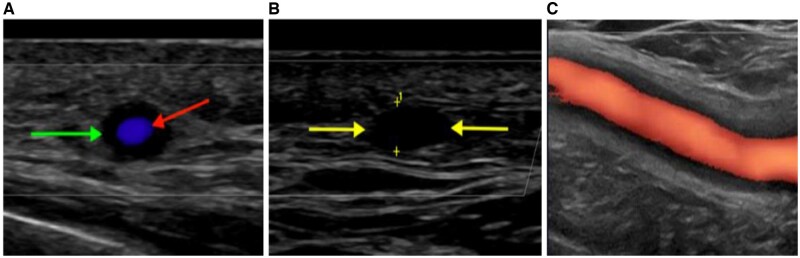

Objectives: Vascular ultrasound (VUS) is a well-validated tool for diagnosing GCA [1]. The role of VUS in prognostication and disease-monitoring remains to be defined.

Methods: This study compares intima-media thickness (IMT), Halo Count (HC), Halo Score (HS) and OMERACT GCA US Score (OGUS) at multiple time points in a prospective cohort of GCA patients to evaluate the role of sonographic vasculitis quantification in the diagnosis and management of GCA. Longitudinal trends and time-to-normalization of HC, HS and OGUS were evaluated. Correlation coefficients, AUC analysis and DeLong test were used to determine which patient factors may predict VUS outcomes and which patient factors are predictive of adverse events.